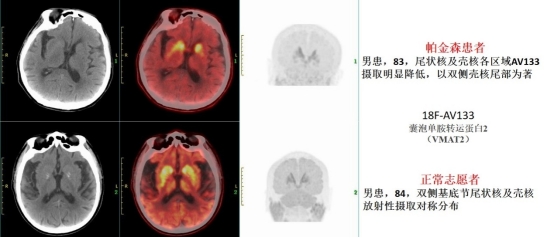

为满足临床医师及广大患者需求,ac米兰官网中文网站肿瘤医院PET/CT-MRI中心在省内率先开展18F-AV133 PET/CT成像,对帕金森病(Parkinson’s disease,PD)进行精准诊断及评估,是我省首次应用18F标记囊泡单胺转运蛋白2(Vesicular monoamine transporter, VMAT2)进行显像。该分子成像特异度、灵敏度高,代谢稳定性好,可反映多巴胺能神经元功能,且不易受外源性多巴胺能药物治疗的影响。辅助临床医师对PD进行早期诊断、病情评估与监测、鉴别诊断,助力龙江人民生命健康。

分子显像是研究PD发病机制的重要工具。核素18F合成产率高、物理半衰期长,ac米兰官网中文网站肿瘤医院PET/CT-MRI中心具备稳定合成18F-AV133的能力,在省内率先利用18F-AV133 PET/CT无创、靶向评估囊泡单胺转运蛋白2(VMAT2)浓度,客观评估黑质——纹状体通路多巴胺能神经元突触前膜情况。不仅可对PD进行早期诊断、病情监测,还可用于PD的鉴别诊断(特发性震颤、肌张力障碍性震颤、药物源性帕金森综合征、心因性帕金森综合征和血管性帕金森综合征等,在临床上与PD有诸多相似之处),达到早发现、早诊断、早治疗,延缓疾病进展,改善患者的生活质量。